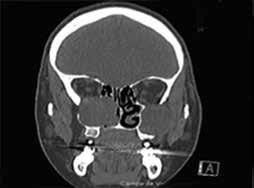

Physical examination revealed a firm, palpable neck mass fixated on the right (figure 1, A). Laryngeal endoscopy showed normal vocal fold movement and a projection of the posterior pharyngeal wall. Magnetic resonance imaging (MRI) revealed an 11-cm mass extending from the right to the left sternocleidomastoid (SCM) muscles (figure 1, B). Surgery was scheduled, with the goal to resect as much tumor as possible and to refer the patient for postoperative radiotherapy.

A B

Figure 1. A: Photo shows the appearance of the neck, with enlargement of the right side and obliteration of the space between the sternocleidomastoid muscle and the larynx. The scar of the previous thyroidectomy is visible. B: T2-weighted MRI of the neck reveals the tumor occupying the space between the larynx and the spine and extending between the large vessels on both sides. The right carotid is enclosed within the tumor.

During surgery, a nasogastric tube was placed as a palpable guide to the esophagus. A right hockey-stick incision, including the previous thyroidectomy incision, was made. After elevation of the subplatysmal flaps, the tumor was found completely occupying the space between the right SCM and the larynx. It was dissected away from the SCM, the larynx, the cervical spine, and the esophagus. The right common carotid was surrounded by the tumor but was palpated and used as a landmark (figure 2). The internal jugular vein was saved, but the right inferior laryngeal nerve was sacrificed. An attachment to the right cricothyroid muscle was noticed as a possible point of tumor origin.

Postoperatively, the patient had bilateral vocal fold palsy, but movement of the left vocal fold returned to normal 3 days later. She also had Horner syndrome on the right side, which improved after 3 months. Her swallowing difficulty immediately resolved, and she was discharged on the fifth day. One month later, a follow-up MRI showed no sign of tumor presence, and it was decided to wait before any additional treatment was undertaken.

Two years later, the patient remains disease-free (figure 3), so she is considered cured. Histology showed the lesion to have the morphologic aspects of extraabdominal fibromatosis.